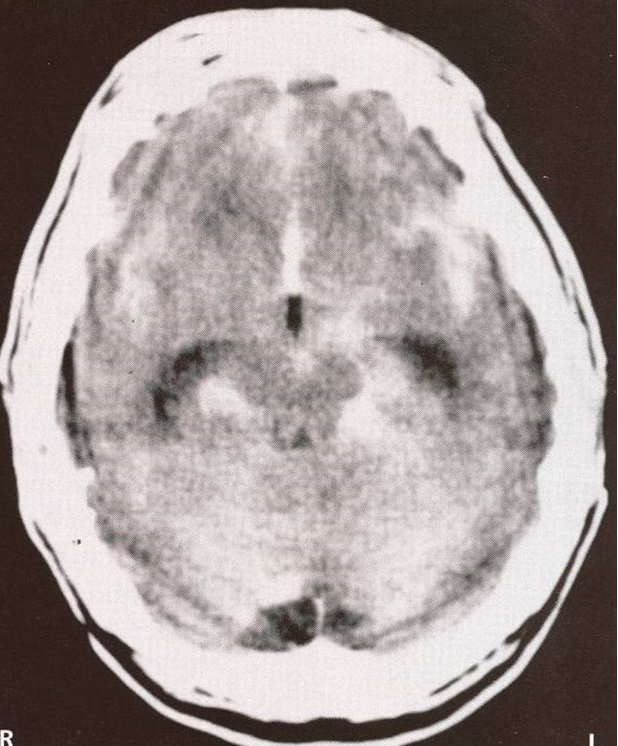

postcentral gyrus, 3, 1, 2

60